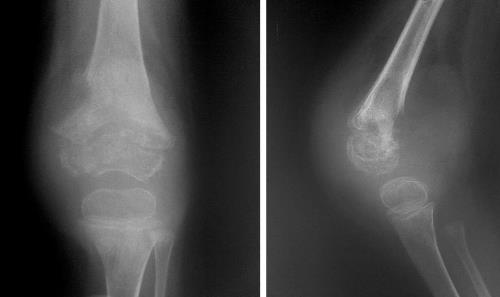

Диагностирование

Диагностирование патологического процесса основано на физикальном осмотре пациента, сбора анамнестических данных. В дополнение показано рентгенологическое исследование костного аппарата. В качестве дополнительных исследований применяют: